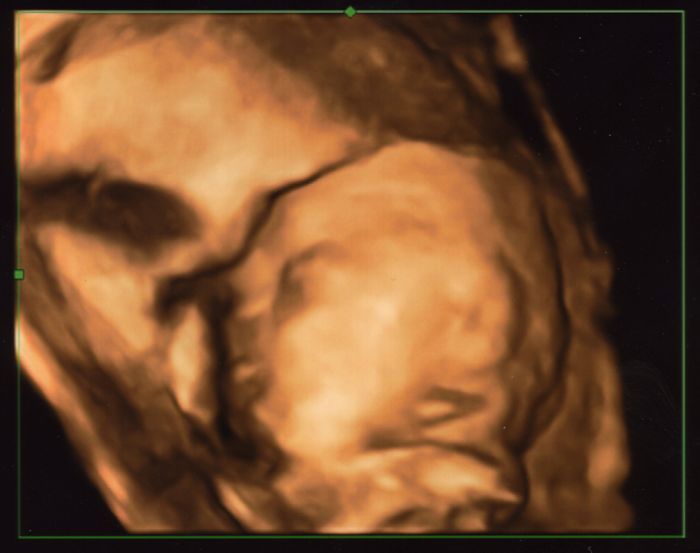

Dobré ráno holky :-) ...tak se večer maličká pěkně vrtěla. Jakoby mi chtěla ukázat, že je živá a zdravá a ať se nebojím :-) Nicméně jsem ráda, že jsem za tím doktorem zašla. Přece jenom po těch potratech nejde občas nemyslet na nejhorší.... Tak tady je spící portrét naší Evelínky :-)